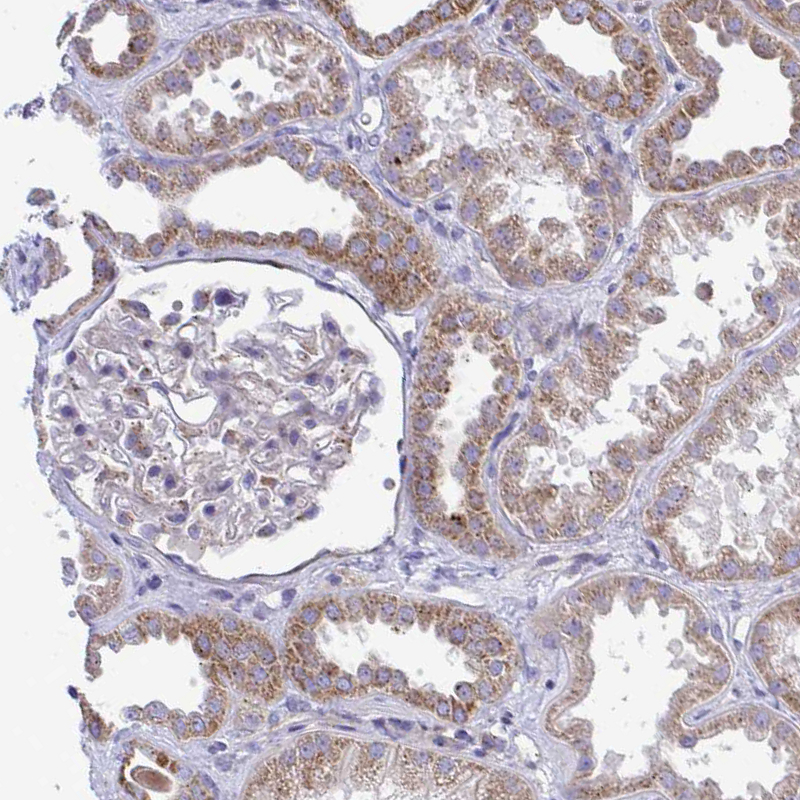

Immunohistochemical staining of human kidney shows weak cytoplasmic granular expression in cells in tubules.